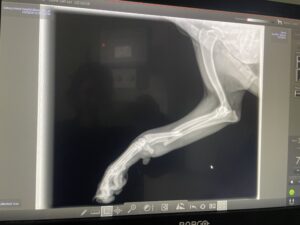

Sierra’s broken leg